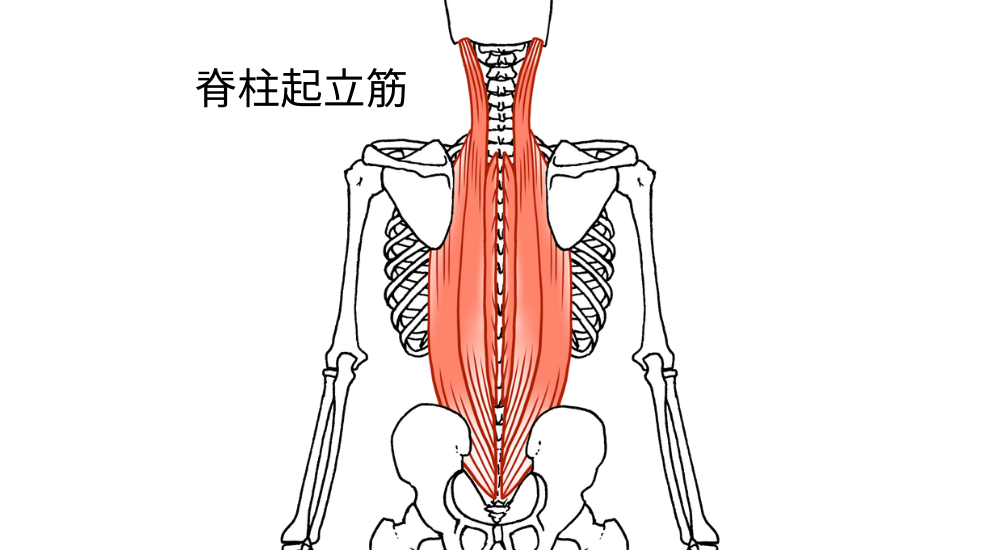

- 背骨周りの筋肉と深層筋(脊柱起立筋、多裂筋など):

背骨の近くには自律神経幹が走行しており、これらの筋肉の緊張や背骨の歪みが自律神経に影響を与える可能性があります。

これらの筋肉の慢性的な緊張は、身体を常に「戦闘モード」に近い状態にさせ、自律神経のバランスを崩すことで、慢性的な疲労感や気分の落ち込みに繋がるのです。